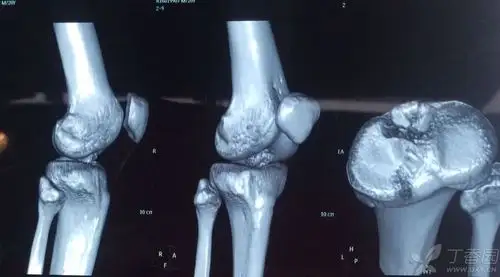

胫骨平台髁间棘图片

早期,骨刺主要体现在髁间嵴,表现为髁间嵴变尖,骨刺继续发展的话,膝

胫骨髁间棘骨折术前mri片子,显示髁间棘骨折!

胫骨髁间棘骨折

胫骨髁间棘骨折术前dr片!